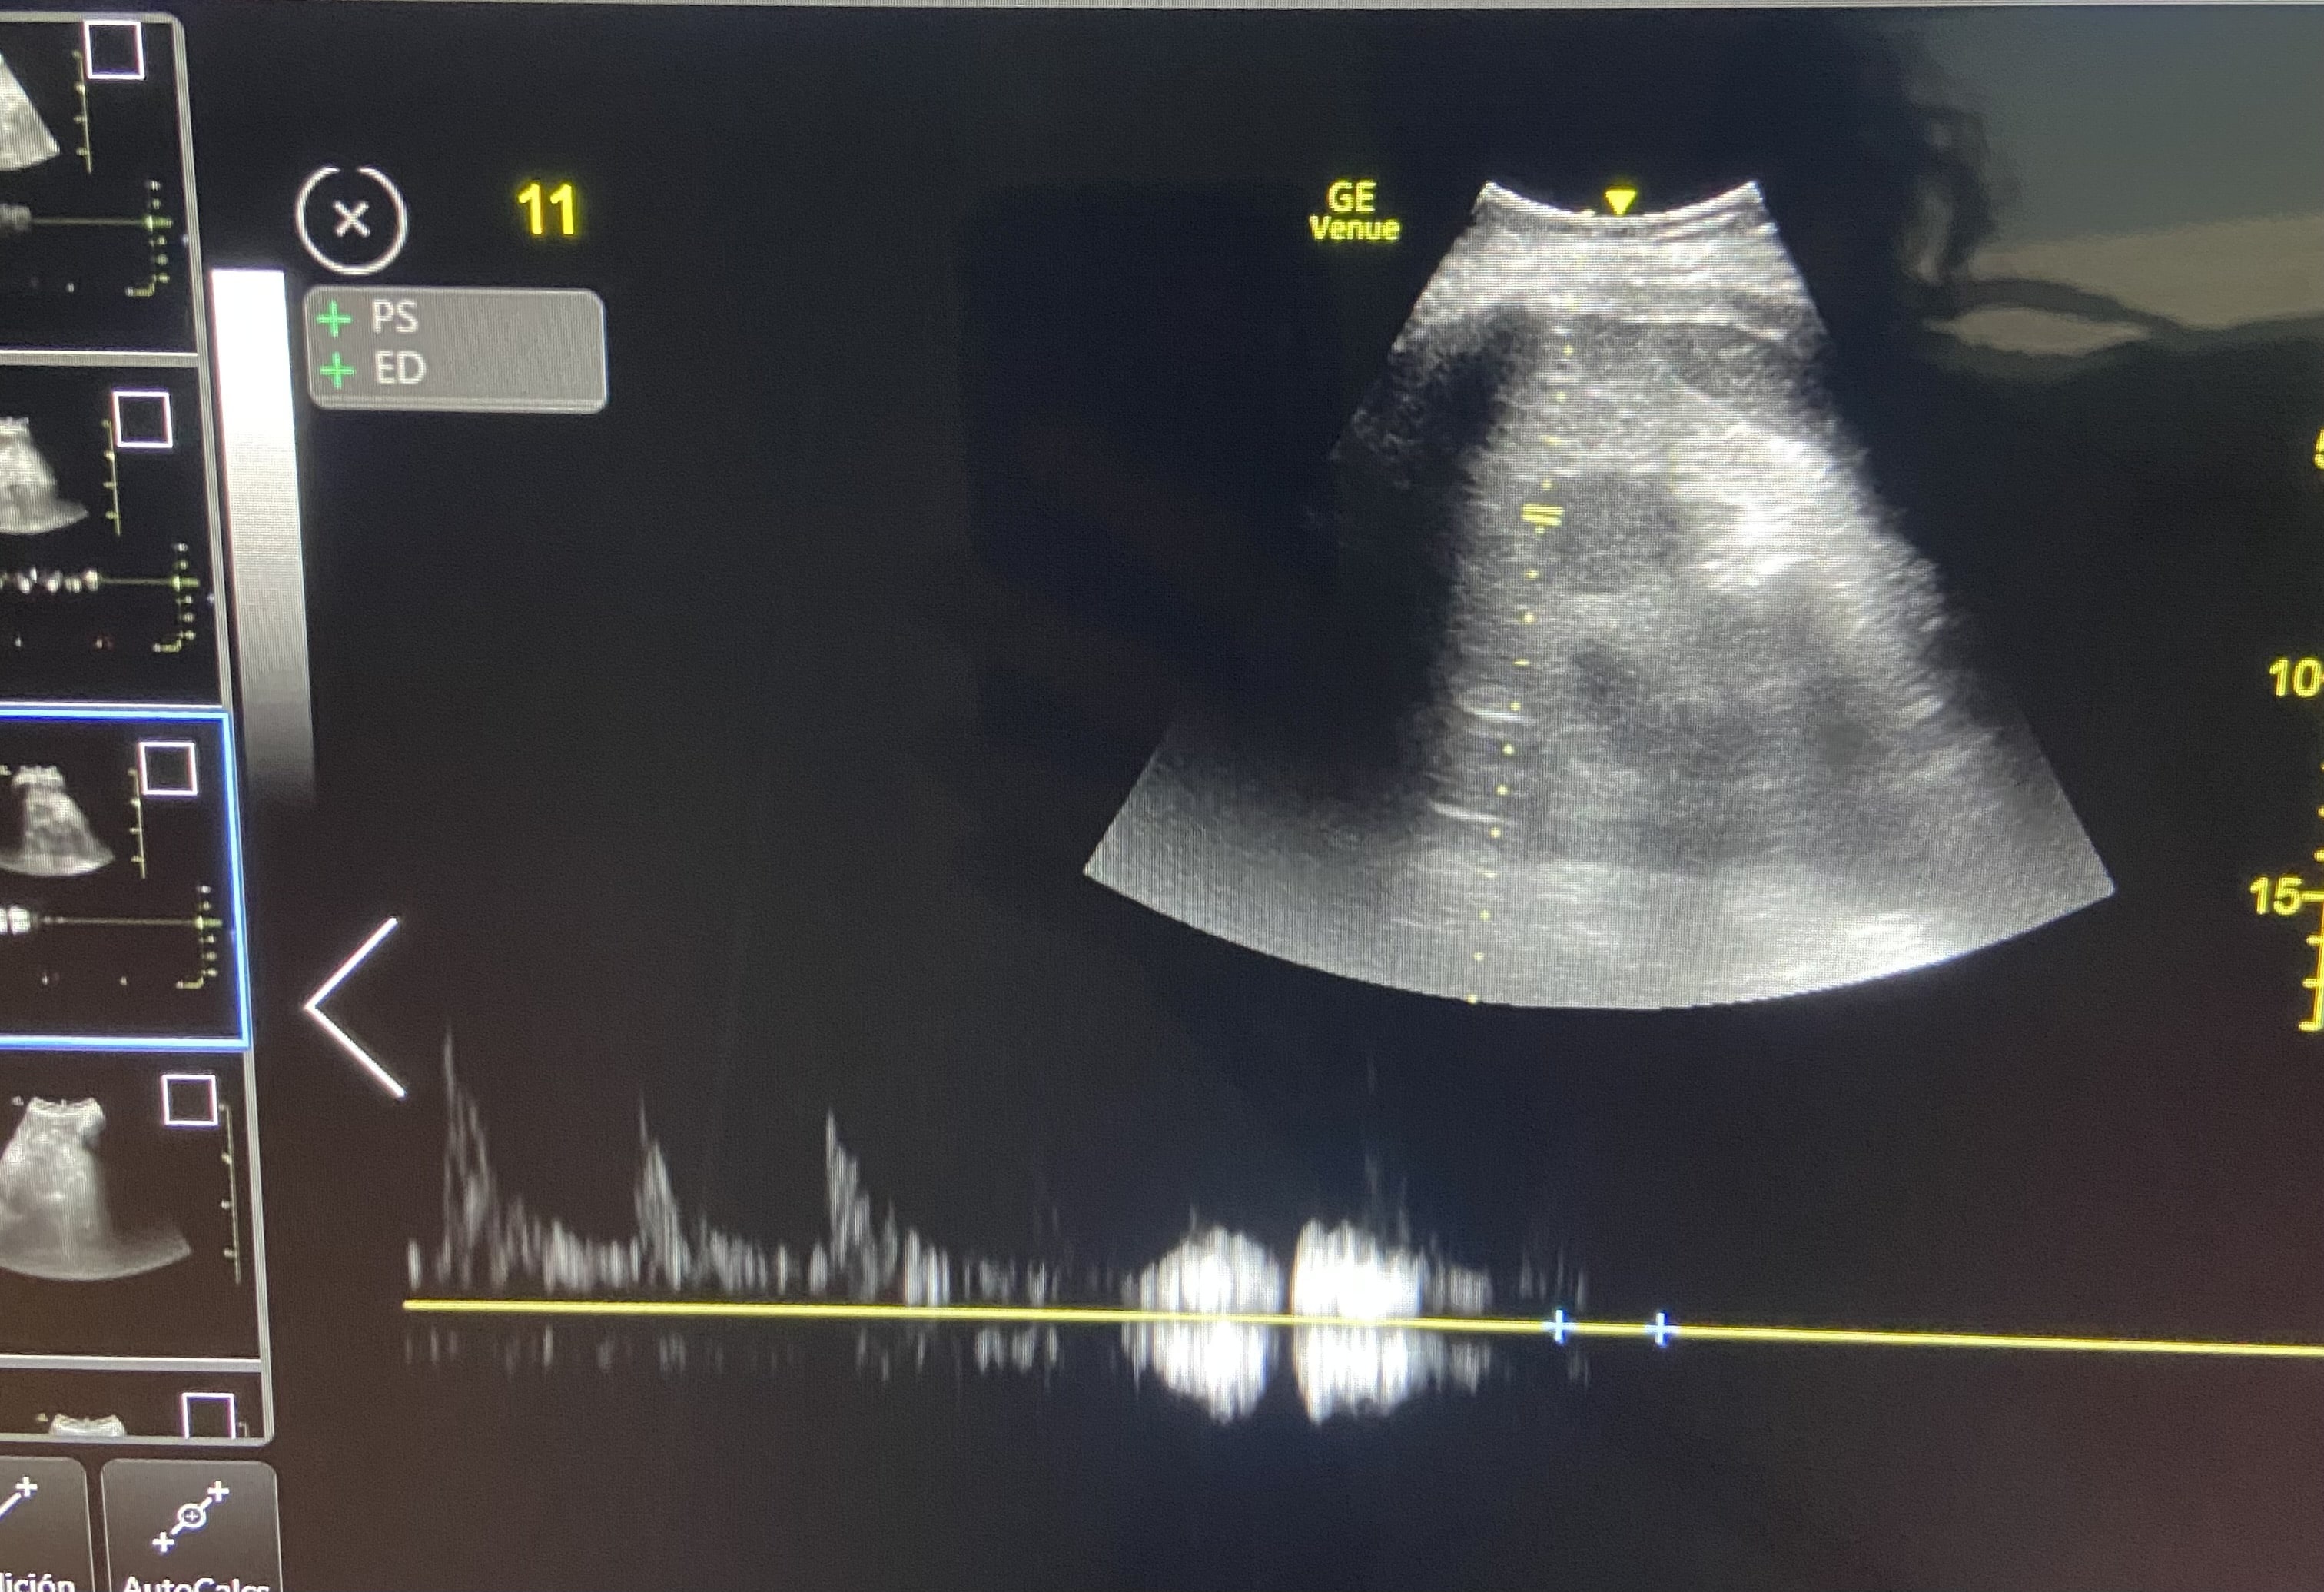

Paciente hombre de 85 años con antecedentes de insuficiencia cardiaca. Acude a urgencias por disnea progresiva de 48 horas de evolución, precedida por 10 días de ingesta deficiente. En la exploración física, presenta crepitantes bibasales hasta campos medios, edemas hasta rodillas, mucosas secas y signo del pliegue positivo. La tensión arterial es de 107/65 mmHg. Los análisis sanguíneos revelaron una creatinina de 1.8 mg/dL y un NT-proBNP de 5500 pg/mL, con una fracción de excreción de urea de 32%, compatible con origen prerrenal. Ante la aparente contradicción, se realiza una ecografía PoCUS dirigida. La vena cava inferior mostró un diámetro máximo de 2,13 cm con colapsabilidad en inspiración, y el Doppler de venas suprahepáticas, venas porta e intrarrenales no evidenció signos de congestión. En conjunto, los hallazgos configuraron un perfil VExUS Grado 1.

Se diagnostica un síndrome cardiorrenal tipo 1. El diagnóstico diferencial se establece entre una otros tipos de síndrome cardiorrenal. La ecografía orientó a una congestión vascular como principal problema a resolver en este caso complejo.

En base al perfil VExUS Grado 1 se inició tratamiento con diuréticos a dosis moderadas para tratar el componente congestivo, sin empeorar el renal.

El paciente mostró una evolución favorable con tratamiento diurético inicial. Una vez hospitalizado, el protocolo VExUS mostró un perfil con menor congestión, por lo que se pudo iniciar fluidoterapia, logrando una normalización de los parámetros renales.

Este caso demuestra que el protocolo VExUS es una herramienta dinámica, esencial para el médico de urgencias en el manejo complejo de la volemia en pacientes cardiorrenales, permitiendo una toma de decisiones segura y eficaz en situaciones clínicas complejas.